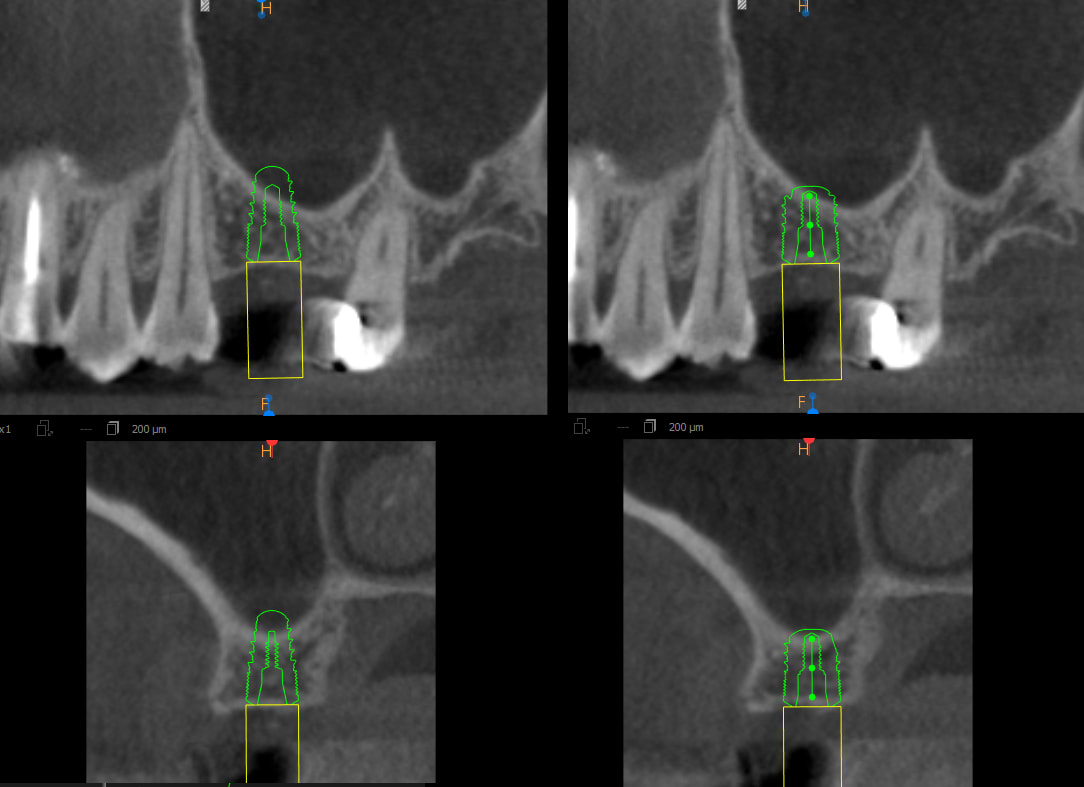

Pour une 16, j’hésite entre un 4.5 x 6, et 4.5 x 8.

Là, c'est pour mon épouse , la membrane est super fine et le plancher en biais.

Vu l'épaisseur/qualité de nonoss sur la coupe frontale, ton Diam4.5 en 6mm aura une ostéointégration de bourrin, tu peux y aller les yeux fermés, franchement c'est du velours, là,non?!

Si t'as 6,5 mm de partout, le débat est pertinent car on discute perfo ou non perfo. Ce n'est pas le cas ici. Dans sa planif, on voie une perfo timide du 6 mm qui n'est pas réaliste, on ne fait pas de demie perfo. Le risque est d'hésiter, sous-forer et ne pas assez enfouir son implant ou de surforer. Avec le 8, tu ne te poses pas de questions et tu fais ça proprement. Il n'est pas rare de voir à 1-2 ans une fine couche d'os se former dans des cas comme ça.